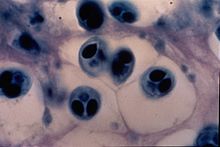

Stade Myxospore

Les Myxospores, qui se développent à partir du stade sporogonic dans les tissus cellulaires du poisson hôte, sont de forme lenticulaire. Elles ont un diamètre d'environ 10 µm, et sont composées de six cellules. Deux de ces cellules forment des capsules polaires, deux autres s'associent pour former un sporoplasme binucléé, et les dernières forment des valves de protection. Les Myxospores sont infectieux pour les oligochètes, que l'on trouve parmi les restes de digestion des poissons cartilagineux. Ils sont souvent difficiles à distinguer des autres espèces en raison des similitudes morphologiques à travers les genres. Si M. cerebralis est le seul Myxosporea trouvé dans le cartilage des salmonidés, d'autre espèces visuellement similaires peuvent être présentes dans la peau, le système nerveux ou musculaire.